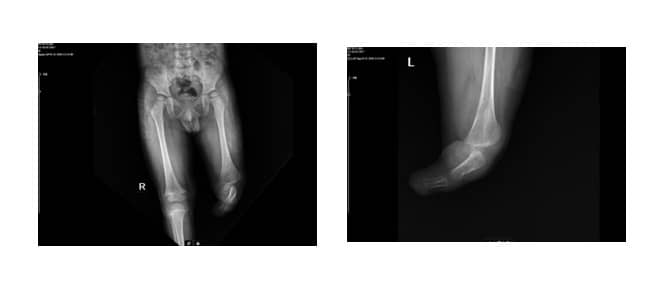

Рентгеновите снимки на пациента показаха пълна агенезия на тибията и фибулата (Фиг. 3 А, В).

Фиг. 3. А: Латерален изглед

B: Антеропостериорен изглед